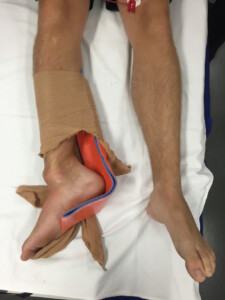

Case 1 - Ankle Injury

A 20 yr old male has his right foot caught under his bike after losing control and falling off at very low speed in his driveway.  He did not have a headstrike. He has had a basic splint applied by paramedics on his way into your ED.

1) Describe the likely injury seen in this photo.